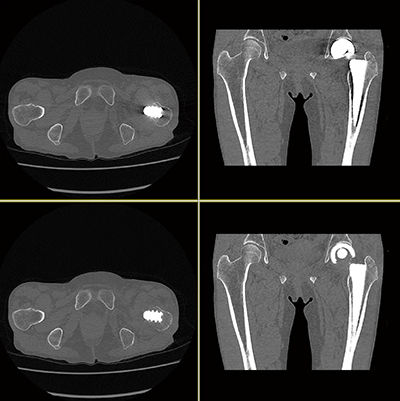

図1 大腿骨転子部骨折症例

SEMARを使用することにより、金属アーチファクトで評価が難しかった骨折線が明瞭に描出できている。